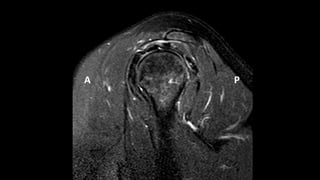

O documento aborda lesões no ombro, dividindo-as por faixas etárias: fraturas de clavícula em crianças, luxações em adultos e fraturas do úmero proximal em idosos. Descreve também técnicas de avaliação radiográfica e suas variações, incluindo incidências específicas para diagnóstico. Além disso, são mencionados métodos de imagem alternativos para a avaliação de partes moles e condições articulares.